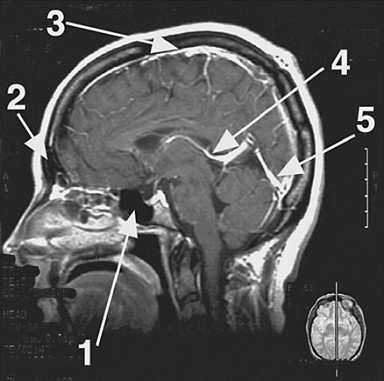

The great cerebral vein of Galen indicated by arrow 4 in following figure is formed by the union of two internal cerebral veins and drains into which of the following?

The great cerebral vein of Galen (arrow 4) drains posteriorly into the straight sinus (arrow 5). The union of the superior sagittal sinus (choice E; arrow 3) and the straight sinus forms the confluence of sinuses (choice A). The straight sinus and superior sagittal sinus are dural venous sinuses: they contain venous blood draining form the brain, skull, and scalp. The frontal sinus (choice B) and the sphenoid sinus (choice C) are bony sinuses: they are hollow, airfilled structures and do not drain venous blood.